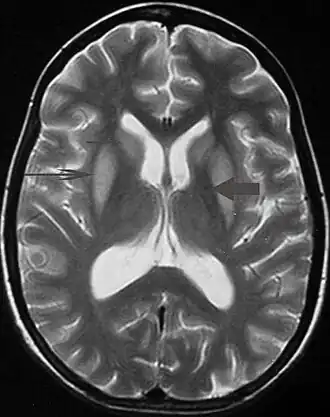

Pode ser diagnosticado clinicamente no contexto apropriado, mas pode ser difícil de confirmar radiologicamente usando técnicas de imagem convencionais. As alterações são mais proeminentes na ressonância magnética (RM) do que na tomografia computadorizada (TC), mas geralmente levam dias ou semanas após o início dos sintomas agudos. A imagem por RM normalmente demonstra áreas de hiperintensidade em imagens ponderadas em T2.[29]